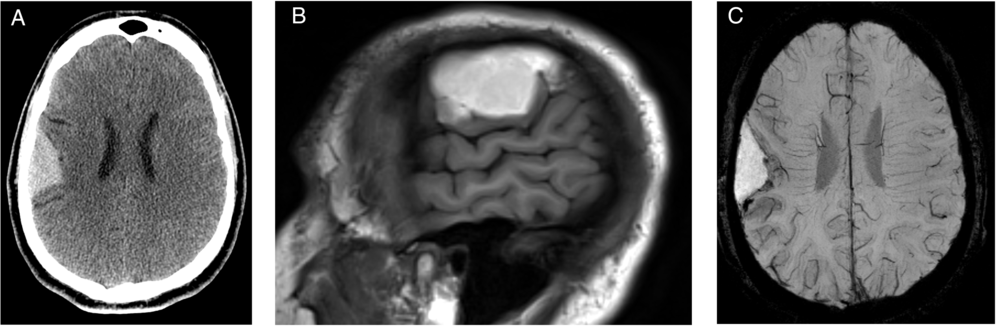

This is a case of a 30-year-old right-handed male patient who presented to the hospital in 2014 after hitting his head on the mat during a wrestling match followed by headache and temporary peripheral vision limitation. The patient’s past medical history was unremarkable. On physical examination, Glasgow Coma Scale was 15 with no focal neurological deficits. Unenhanced head computed tomography (CT) and enhanced brain magnetic resonance imaging (MRI) were performed (Figure 1). The patient was managed conservatively, and follow-up CT and MRI in 2015 (Figure 2) demonstrated significant decrease in size of the previously seen right frontoparietal lesion with also changes in its radiological features. The patient remained asymptomatic for about 3 years when in 2018 he presented to the Emergency Department with increasing headaches and peripheral vision loss. MRI demonstrated an increase in the right frontal lesion size (Figure 3). He underwent surgical resection of the lesion.

Figure 2: Follow-up CT and MRI after 1 year: Axial CT (A) and MRI sagittal T1-weighted images (B) demonstrated a decrease in size and changes in the internal content of the cystic lesion, which became completely hyperdense on CT and hyperintense on MRI T1-weighted images. Axial susceptibility-weighted imaging (SWI) demonstrated a rim of blooming artifact in the periphery of the lesion, likely secondary to previous hemorrhage (C).